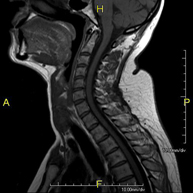

- RM de columna cervical

Prova diagnòstica no invasiva que consisteix en l'obtenció d'imatges d'alta definició anatòmica de la columna cervical mitjançant l'ús d'un camp electromagnètic i ones de ràdio (com un emissor i un receptor). No utilitza radiació ionitzant. Indicacions: traumatisme, degeneració de la columna, hèrnies. - RM de columna dorsal

Prova diagnòstica no invasiva que consisteix en l'obtenció d'imatges d'alta definició anatòmica de la columna cervical, mitjançant l'ús d'un camp electromagnètic i ones de ràdio (amb un emissor i un receptor). No utilitza radiació ionitzant. Indicacions: traumatisme, degeneració de la columna i hèrnies. - RM Columna Dorsal